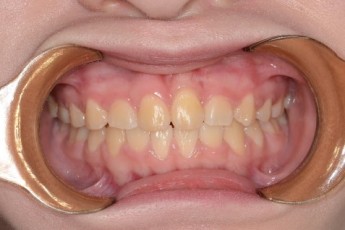

Before & After

- 덧니교정

Before

After